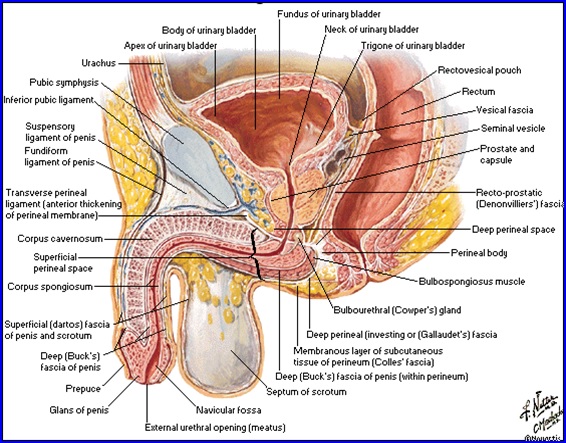

VEZICA URINARĂ (la bărbat)

- Rezervor musculo-membranos cu rol în acumularea, stocarea şi evacuarea urinii.

- Vezica goală: faţa anterioară, posterioară, inferioară (fundul), col.

- Vezica plină: adaugă 2 feţe laterale.

Raporturi:

- Posterior:

- peritoneu - uter, rect;

- colon sigmoid;

- anse intestinale;

- apendice.

- Anterior:

- spaţiul prevezical (fascia ombilico-prevezicală şi fascia transversalis);

- perete anterior al pelvisului;

- Baza

- Barbat: segment prostatic; Spatiul veziculo-deferenţial: vezicule seminale, ampulele deferenţiale, ampula rectală.

Vezica urinara barbati:

Uretra

Este canalul prin care urina este expulzată din vezica.

Prostata

Glandă situată în spaţiul pelvisubperitoneal, sub vezica urinară dezvoltată în jurul porţiunii iniţiale a uretrei masculine.

Formă de con cu baza spre vezică.

Dimensiuni: 4/3/3cm.

Loja prostatică:

- Anterior: oasele pubiene;

- Posterior: septul rectovezical Denonvilliers;

- Iinferior: diafragma urogenitală;

- Superior: lig. pubo-prostatice, fundul vezicii, ductele deferente, veziculele seminale.

Vascularizaţie:

- Arterială: din aa. vezicale inferioare, rectale mijlocii şi ruşinoase interne.

- Venoasă: venele prostatei drenează în plexul venos periprostatic care are conexiuni cu v. dorsală profundă şi v. hipogastrică